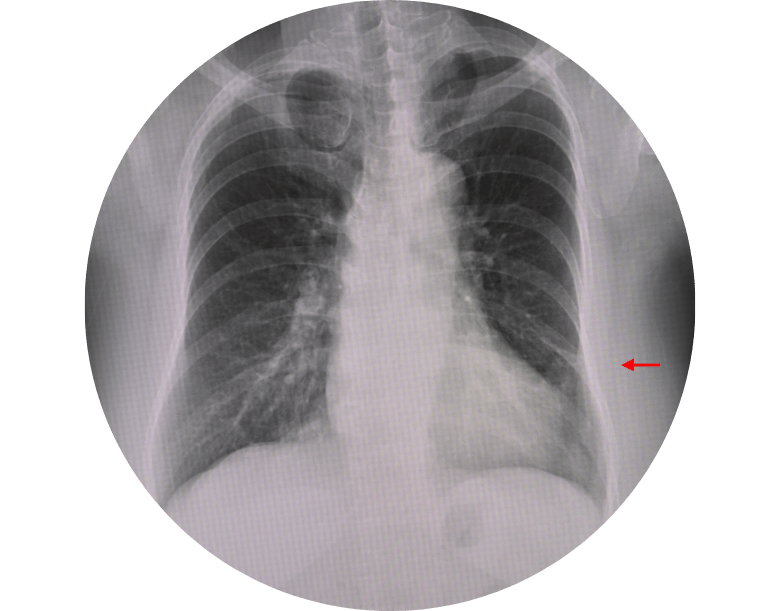

Akciğer röntgeni: En sık kullanılan yöntemdir.